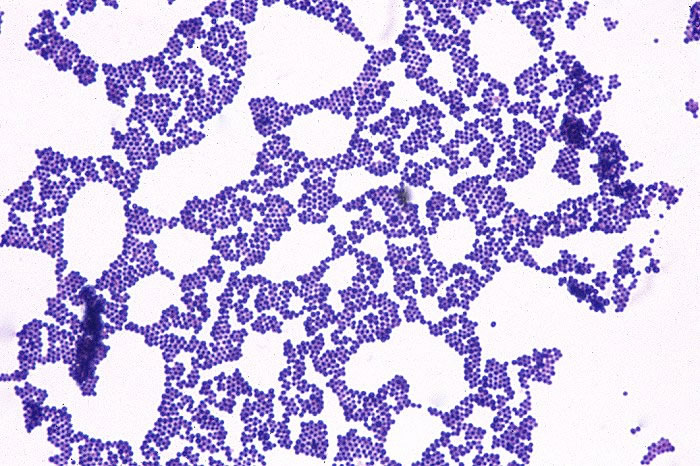

dfgfd/Staphylococcus_Culture.jpg